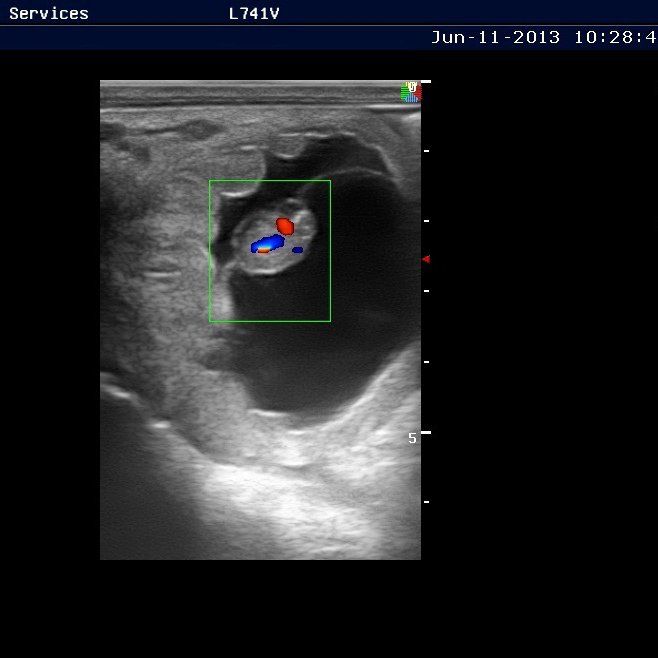

Our reproductive services include embryo transfer, oocyte collection and Intracytoplasmic Sperm Injection (ICSI), semen freezing, breeding with cooled and frozen semen and breeding problem mares. In addition to these specialized services, we also provide extensive on-farm breeding program management.